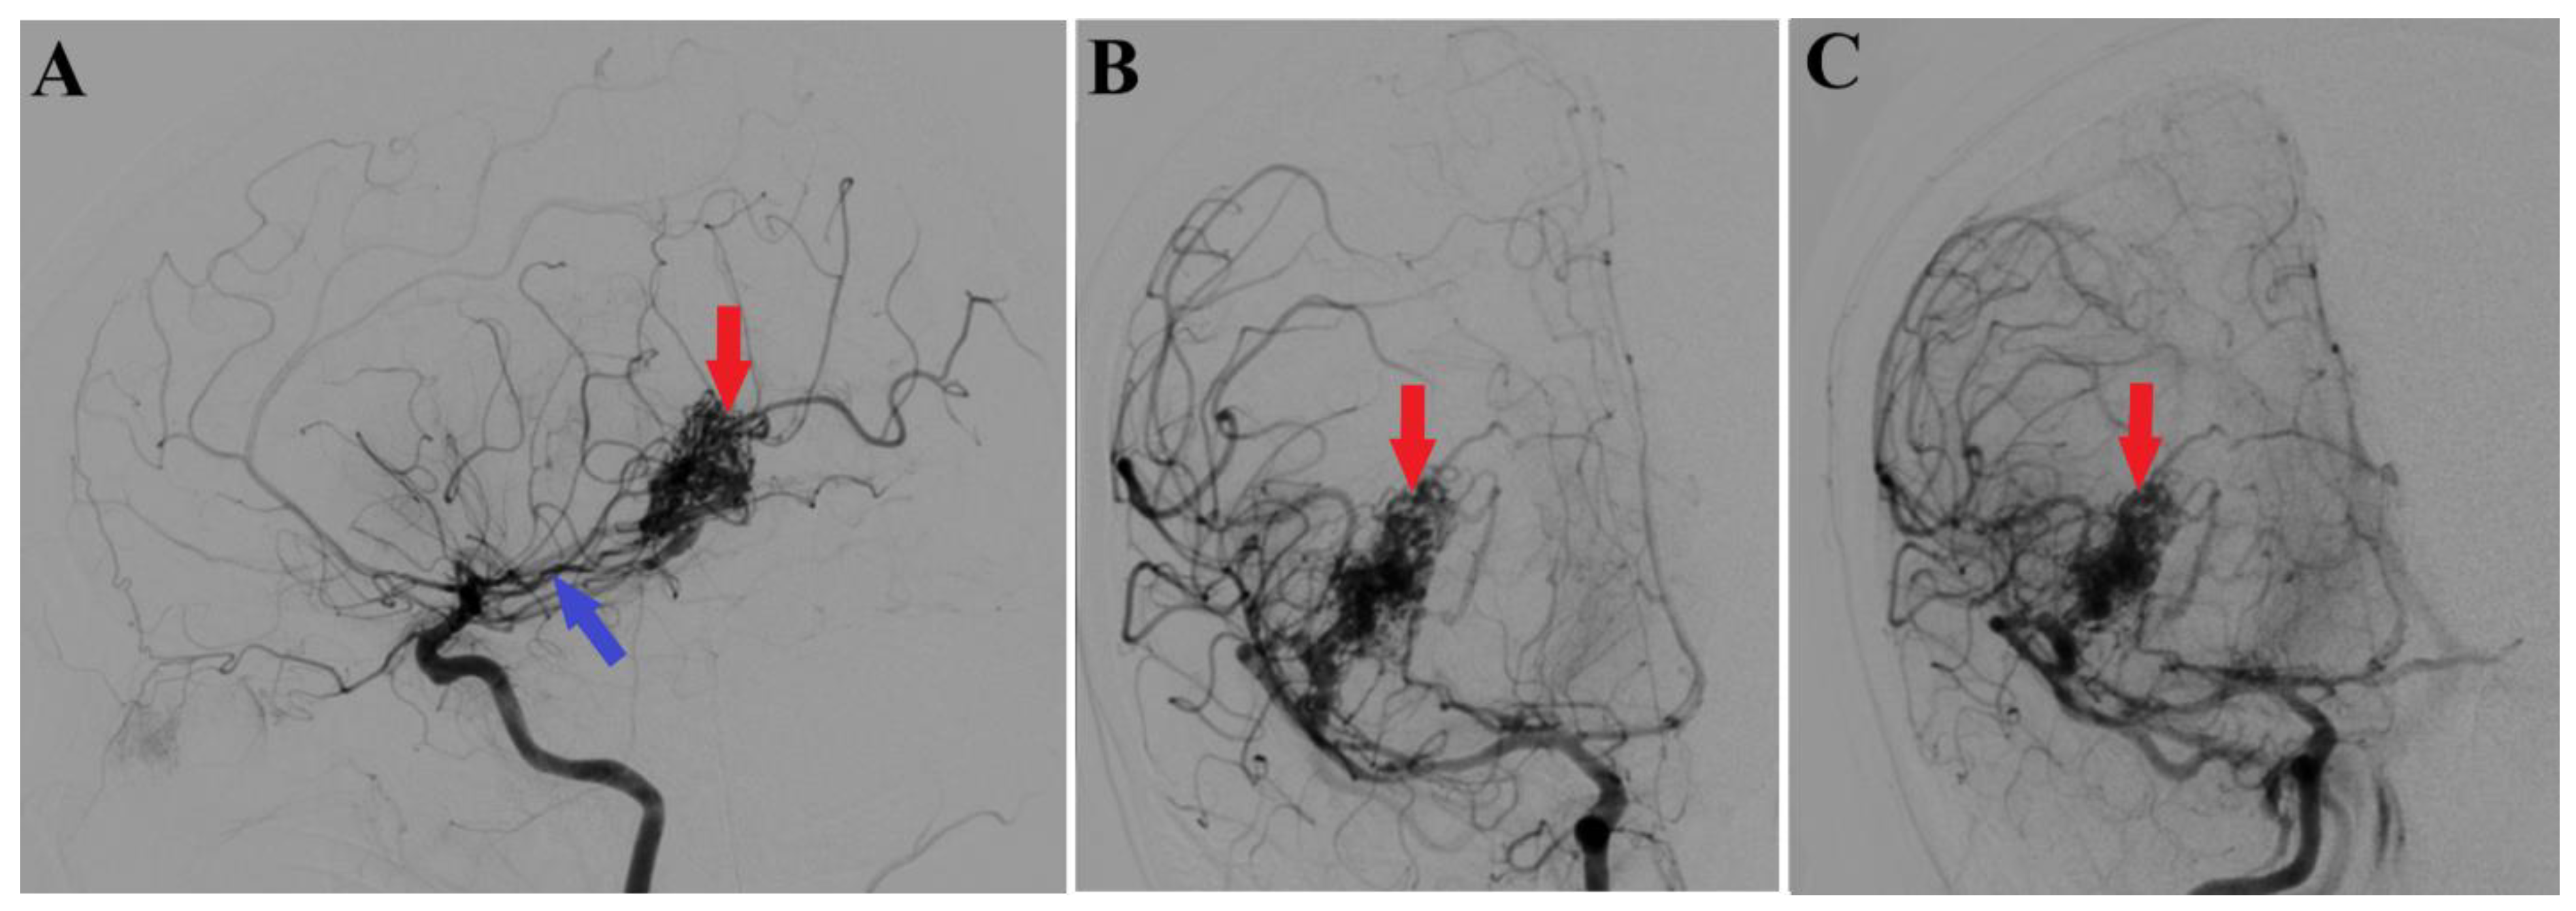

Figure 2.

Preoperative 2D digital subtraction angiography. Profile (A) and frontal (B) 2D DSA highlights the right temporal arteriovenous malformation (red arrows), found as well in 2D DSA reconstruction (C). Moreover, profile 2D DSA (A) shows a slight dilatation of the anterior choroidal artery (blue arrow).

A 44-year-old patient was admitted to our clinic for sudden left hemiparesis MRC 1/5 occurring in the apparent health status 48 h prior to admission, followed by the deterioration of consciousness that become gradually worse, with the patient becoming comatose. She was admitted to our clinic with GCS = 7 points (eye response—2 points, verbal response—2 points, motor response—3 points), orotracheally intubated, and mechanically ventilated. Neurological examination on admission revealed a left hemiparesis, predominantly in the brachial region and comatose state. A brain non-contrast CT scan revealed a voluminous right fronto-temporal intraparenchymal hematoma with panventricular infiltration, significant mass effect on the right lateral ventricle, and 1.5 cm displacement of the midline. Otherwise, normal cerebroventricular CT appearance was seen (Figure 1). Angiography was performed through the selective injection of the internal carotid artery bilaterally, right external carotid artery, and left vertebral artery. Right temporal arteriovenous malformation with arterial afferents from the right anterior choroidal artery and right-sided middle cerebral artery was observed, Spetzler Martin grade III (Figure 2). A nidus of approximately 2/1 cm in size with several intranidal aneurysms was also observed (Figure 3). A single vein was draining into the right cavernous sinus, through an intermediate venous source.